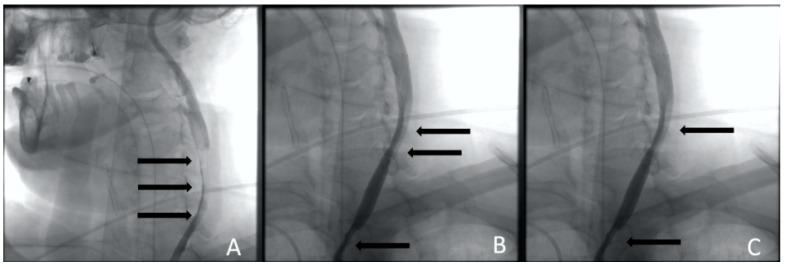

A type A aortic dissection (TAAD) is a dangerous condition requiring emergency surgery. Due to the similarity of the symptoms of cerebral malperfusion in TAAD and the signs of ischemic stroke, a differential diagnosis of these diseases is not always available. Patients with TAAD after cerebral malperfusion can have a neurological deficit. Thrombolysis is performed in this case. It can worsen the patient's condition and increase the risk of mortality and disability. The aim of the study is to evaluate the new approach to restoring cerebral perfusion during aortic dissection. This approach includes endovascular recanalization and carotid stenting.

Two clinical cases of TAAD complicated by cerebral malperfusion are described. The first patient is 73 years old and was admitted as planned to perform transcatheter aortic valve implantation (TAVI) for grade III aortic stenosis. The patient underwent transcatheter aortic valve implantation (TAVI) on the second day after admission. The second patient is 60 years old and was hospitalized by an ambulance with strong hypertension and ischemia. The surgical correction of aortic dissection was postponed until the neurological status assessment in both patients.

The surgery to correct the aorta dissection was deemed inappropriate. The carotid arteries have been reanalyzed, and cerebral perfusion has been restored in a short time in both patients.

Acute bilateral internal carotid occlusion is a potentially fatal TAAD outcome. Emergency endovascular recanalization and carotid stenting may be considered one of the few ways to restore cerebral perfusion.